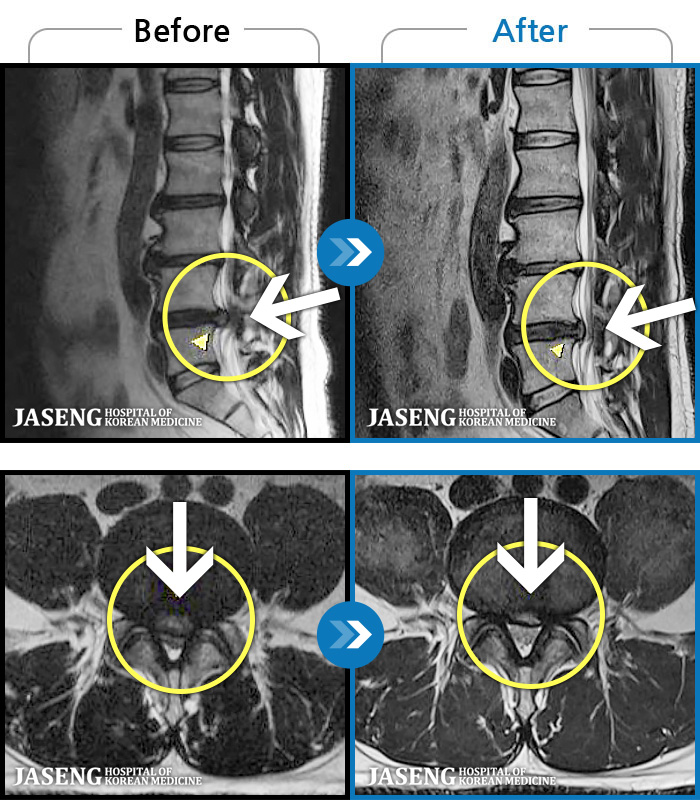

[] 03.04.01~09.11.01